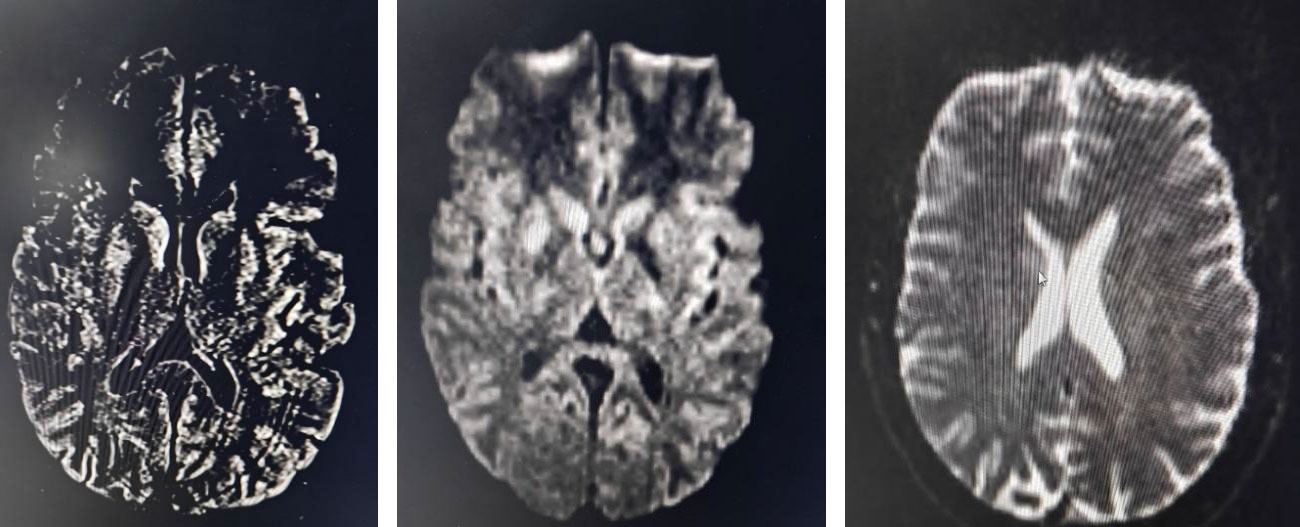

MRI brain (stroke fast protocol) revealed diffusion-weighted hyperintensity with corresponding low ADC values in the right caudate nucleus and lentiform nucleus, confirming an acute infarct

of the right basal ganglia.

FLAIR sequence demonstrated matching hyperintensity.